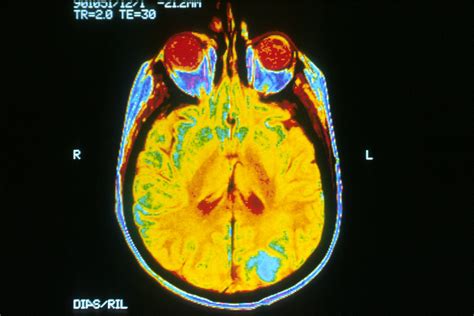

A HC (head circumference), vagyis a fejkörfogat mérése az egyik legstabilabb indikátora a magzati kornak és a fejlődés ütemének, különösen a második trimesztertől kezdődően. A fejkörfogat mérése azért bír kiemelt relevanciával, mert a magzat agyának növekedése közvetlen hatással van a koponyacsontok tágulására.

Az orvosi protokoll szerint a mérést egy speciális anatómiai síkban kell elvégezni, ahol látható a thalamus és a cavum septum pellucidum nevű agyi struktúra. Ez garantálja, hogy minden alkalommal ugyanabban a magasságban történjen a mérés, így az eredmények összehasonlíthatóak maradnak a hetek múlásával. A technológiai fejlődés ellenére fontos szem előtt tartani, hogy a becsült értékek és a születéskori valós adatok között lehetnek eltérések.